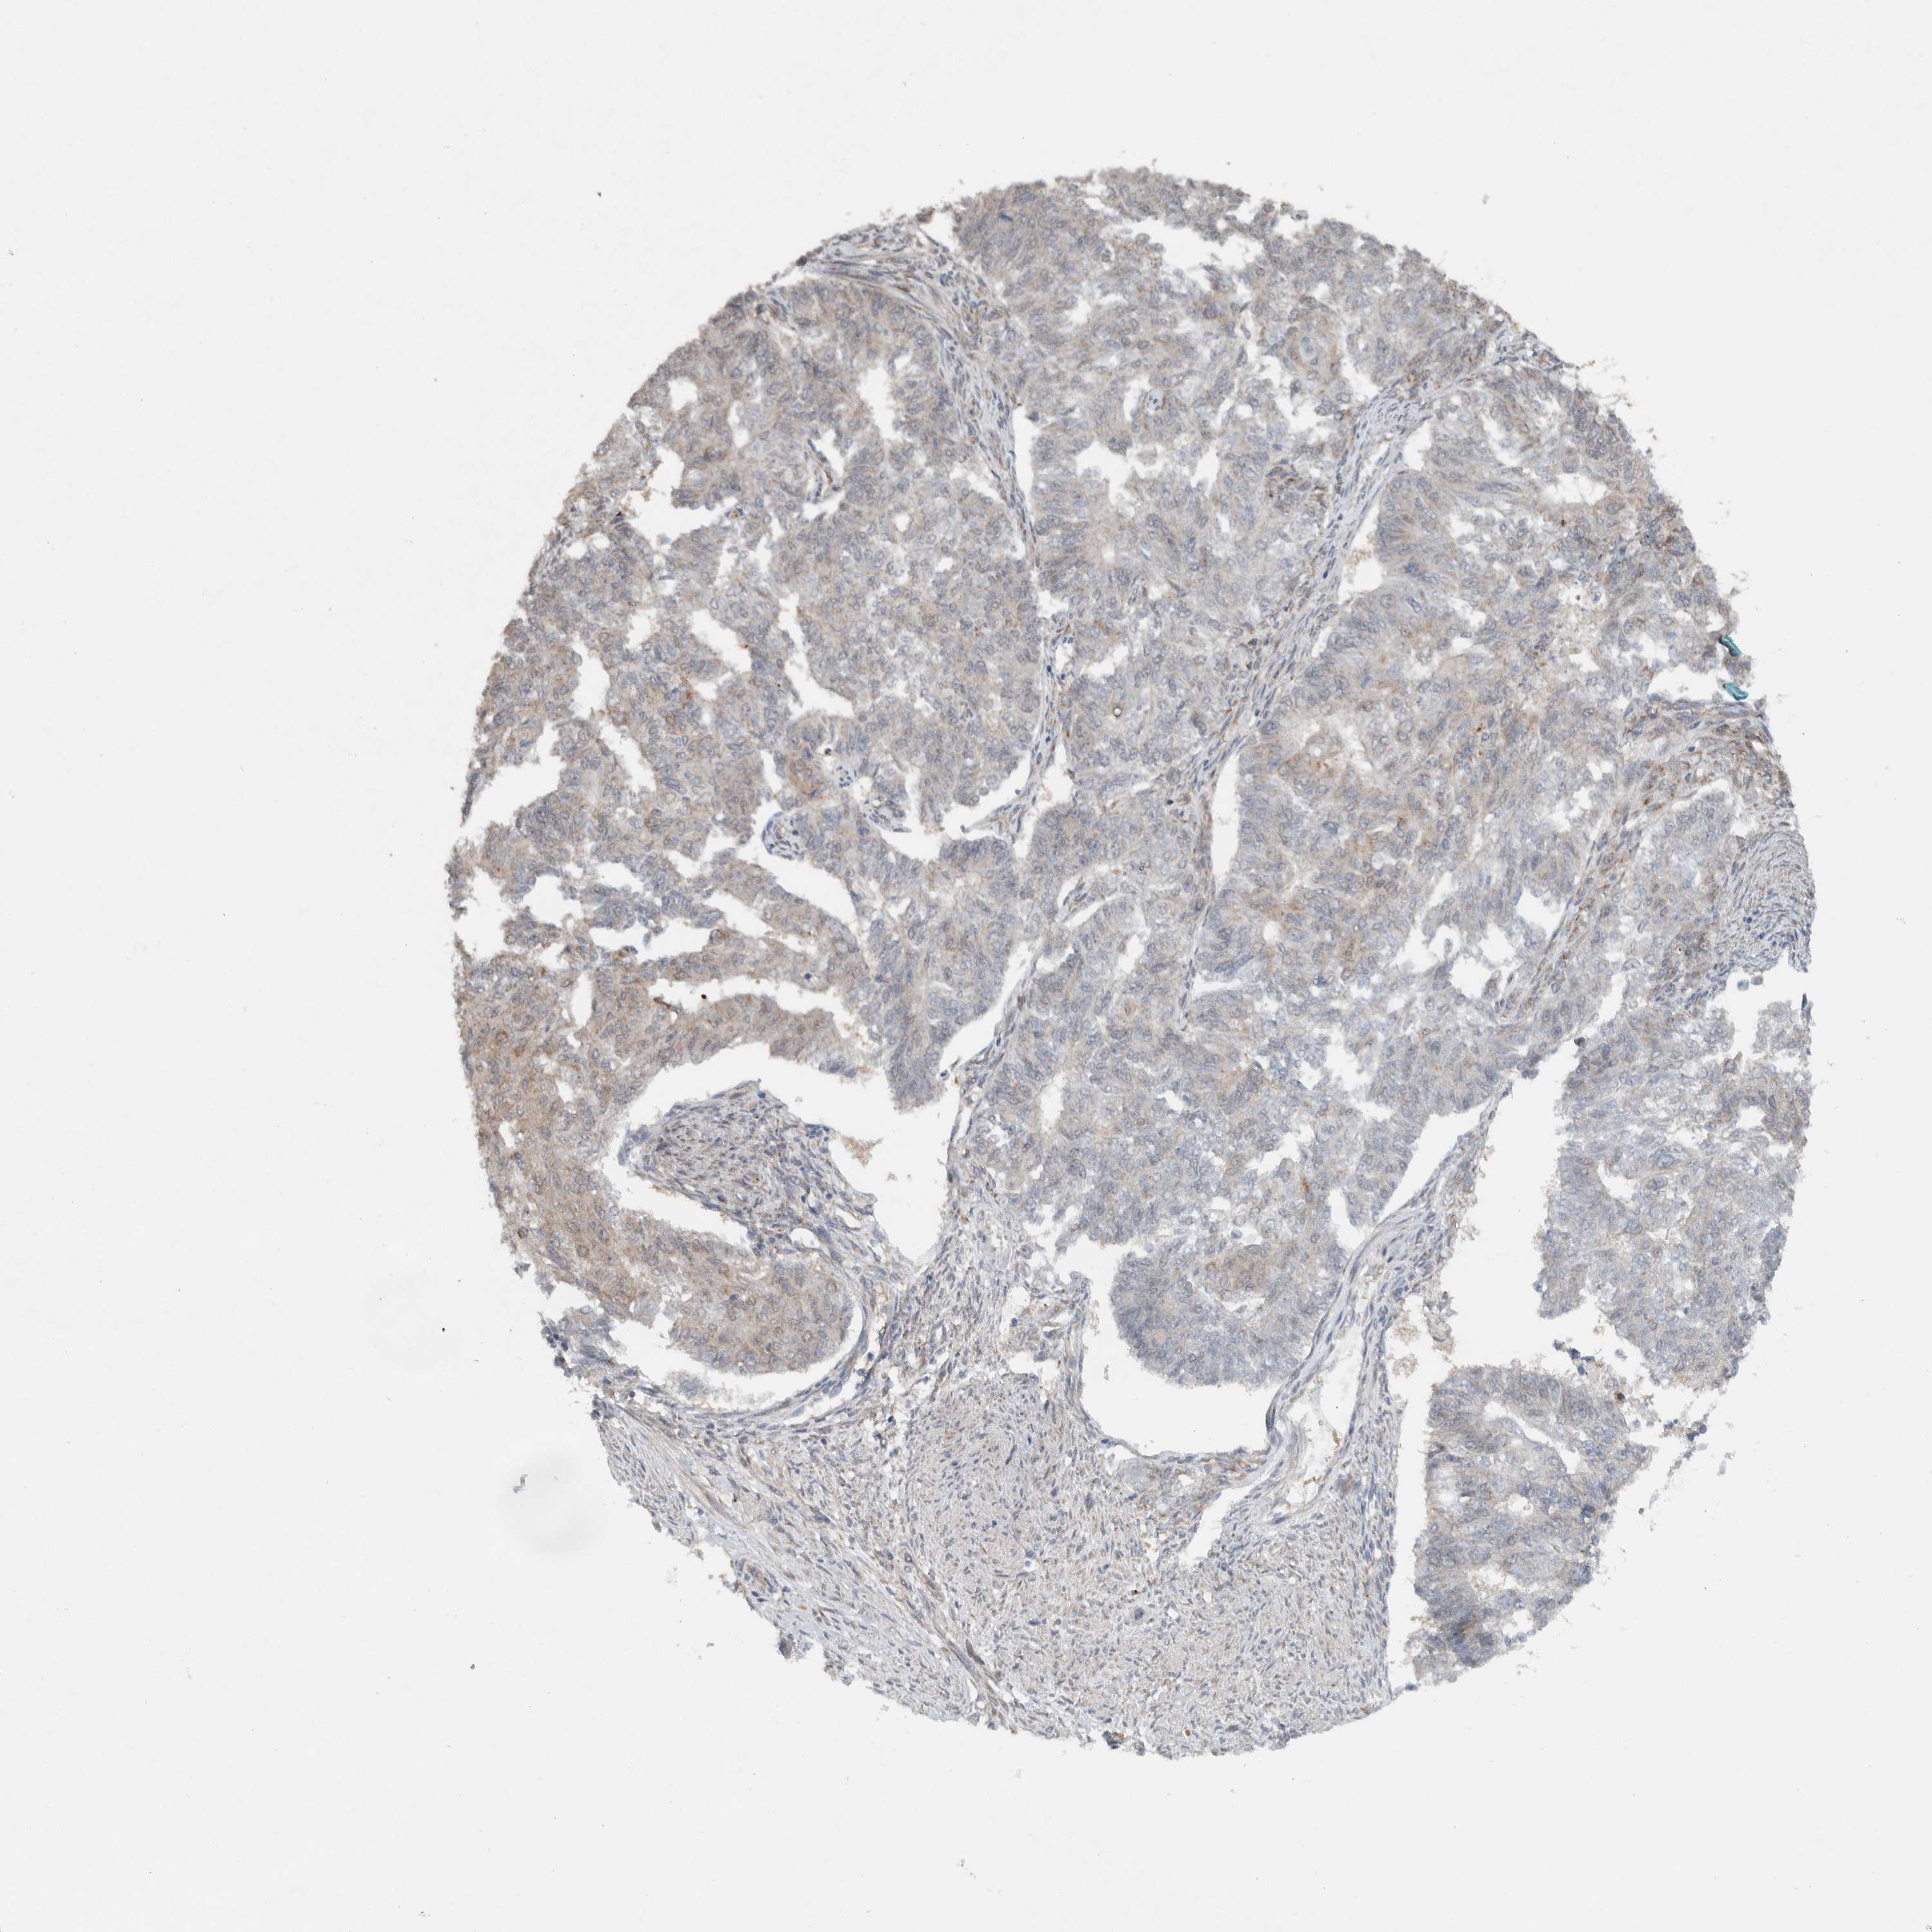

ENDOMETRIAL CANCER - Protein expressioni

A mouse-over function shows sample information and annotation data. Click on an image to view it in a full screen mode. Samples can be filtered based on level of antibody staining by selecting one or several of the following categories: high, medium, low and not detected. The assay and annotation is described here.

Note that samples used for immunohistochemistry by the Human Protein Atlas do not correspond to samples in the TCGA dataset.

Antibody stainingi

Antibody staining in the annotated cell types in the current human tissue is reported as not detected, low, medium, or high, based on conventional immunohistochemistry profiling in selected tissues. This score is based on the combination of the staining intensity and fraction of stained cells.

Each image is clickable and will lead to virtual microscopy that enables deeper exploration of all samples and also displays staining intensity scores, fraction scores and subcellular localization as well as patient and tissue information for each sample.

Antibody HPA024093

Staining

High

Medium

Low

Not detected

Intensity

Strong

Moderate

Weak

Negative

Quantity

>75%

75%-25%

<25%

None

Location

Nuclear

Cytoplasmic/membranous

Cytoplasmic/membranous,nuclear

Adenocarcinoma, NOS